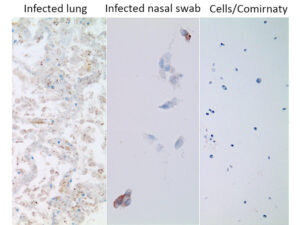

6. Infected persons express the nucleocapsid protein (and also the spike protein)

This slide simply illustrates that the method works: lung tissue or cells from a nasal swab of a person infected with SARS-CoV-2 stain positive for nucleocapsid expression, whereas cultured cells exposed to the vaccine do not (but they stain strongly positive for the spike protein; see inset at the top right of Slide 3).